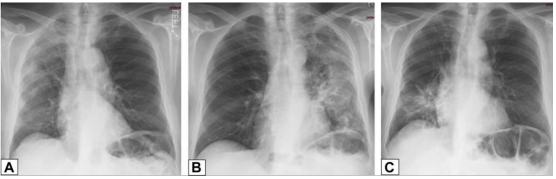

(3)肉芽肿性OP(GOP):图23活检标本显示除了多发性非干酪性肉芽肿(粗箭头)外,还有结节状浸润,提示OP模式。高倍镜显示远端气腔内疏松结缔组织的腔内息肉样栓子(F中细箭头),邻近圆形上皮样组织细胞形成的非干酪性肉芽肿(F中粗箭头)。

图23 肉芽肿性OP

图源:Chest, 2022, 162(1):156-178.OP的诊断主要通过临床表现、影像学及病理表现进行综合判断。如果患者的临床表现、影像学提示OP或病理结果提示OP,并能找到继发因素,可以诊断SOP。如果肺部影像学提示OP(实变、结节或条带/网状OP模式),排除感染或结缔组织病,可行病理检查,如果病理为典型的OP改变,可以诊断COP。(1)多发型片状肺泡渗出影:需与嗜酸性粒细胞肺炎(慢性)、肺泡细泡癌-肺炎型、原发性肺淋巴瘤、吸入性肺炎及其他疾病[如感染性肺炎、结核或非结核性分枝杆菌感染、肉芽肿并血管炎(韦格氏肉芽肿)、弥漫性肺泡出血、多发性肺梗死进行鉴别。(2)孤立性灶性结节或肿块:需与肺癌、炎性假瘤及其他结节或肿块疾病进行鉴别。(3)进行性/致纤维化型COP:与特发性间质性肺炎(尤其是非特异性间质性肺炎和特发性肺纤维化急性加重)以及其他感染、肿瘤性病变进行鉴别。对于COP,目前主要是经验性治疗,因为没有进行前瞻性、随机的治疗试验。<10%的患者(已报道的)可自发缓解,主要见于病情较轻(症状少,病变范围有限)或有禁忌证或已拒绝治疗的患者。SOP需要治疗基础疾病(结缔组织病、感染)或撤除致病药物或暴露,并可能需要更短时间激素治疗(如果疾病病因已经撤除)。